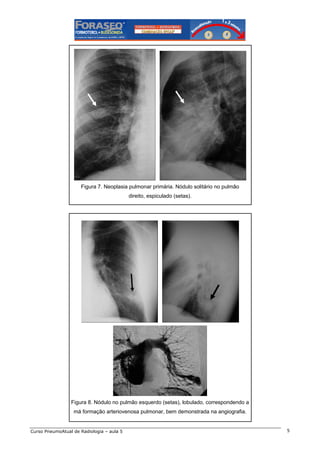

Figura 7. Neoplasia pulmonar primária. Nódulo solitário no pulmão

direito, espiculado (setas).

Figura 8. Nódulo no pulmão esquerdo (setas), lobulado, correspondendo a

má formação arteriovenosa pulmonar, bem demonstrada na angiografia.